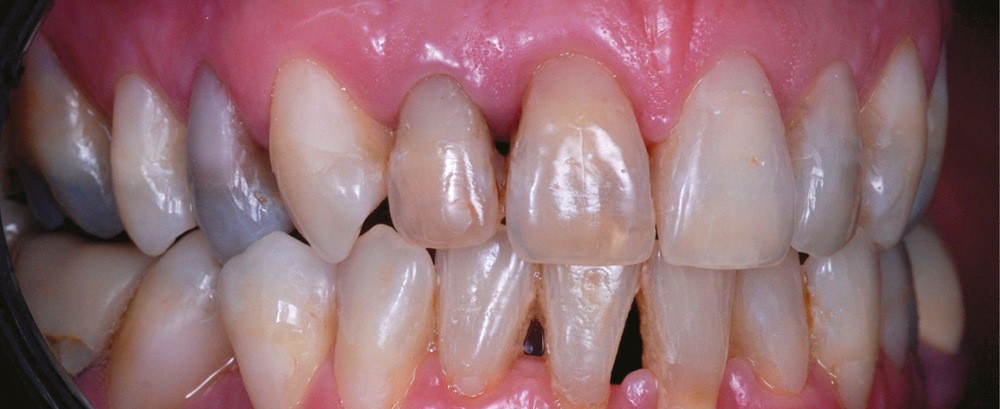

La discoloration de la dent dépulpée est due à trois causes principales :

– la nécrose, qui va donner une coloration plutôt brune [3] (fig. 1, 2) ;

– le trauma, qui va donner une couleur plutôt rouge [4] (fig. 3) ;

– les soins conservateurs et endodontiques [5] (fig. 4 et 5).

Les soins conservateurs et endodontiques sont majoritairement responsables des dyschromies des dents dépulpées. Nous allons développer ce point afin de mieux comprendre les paramètres régissant les colorations iatrogènes pour mieux les éviter et, si besoin, les corriger.